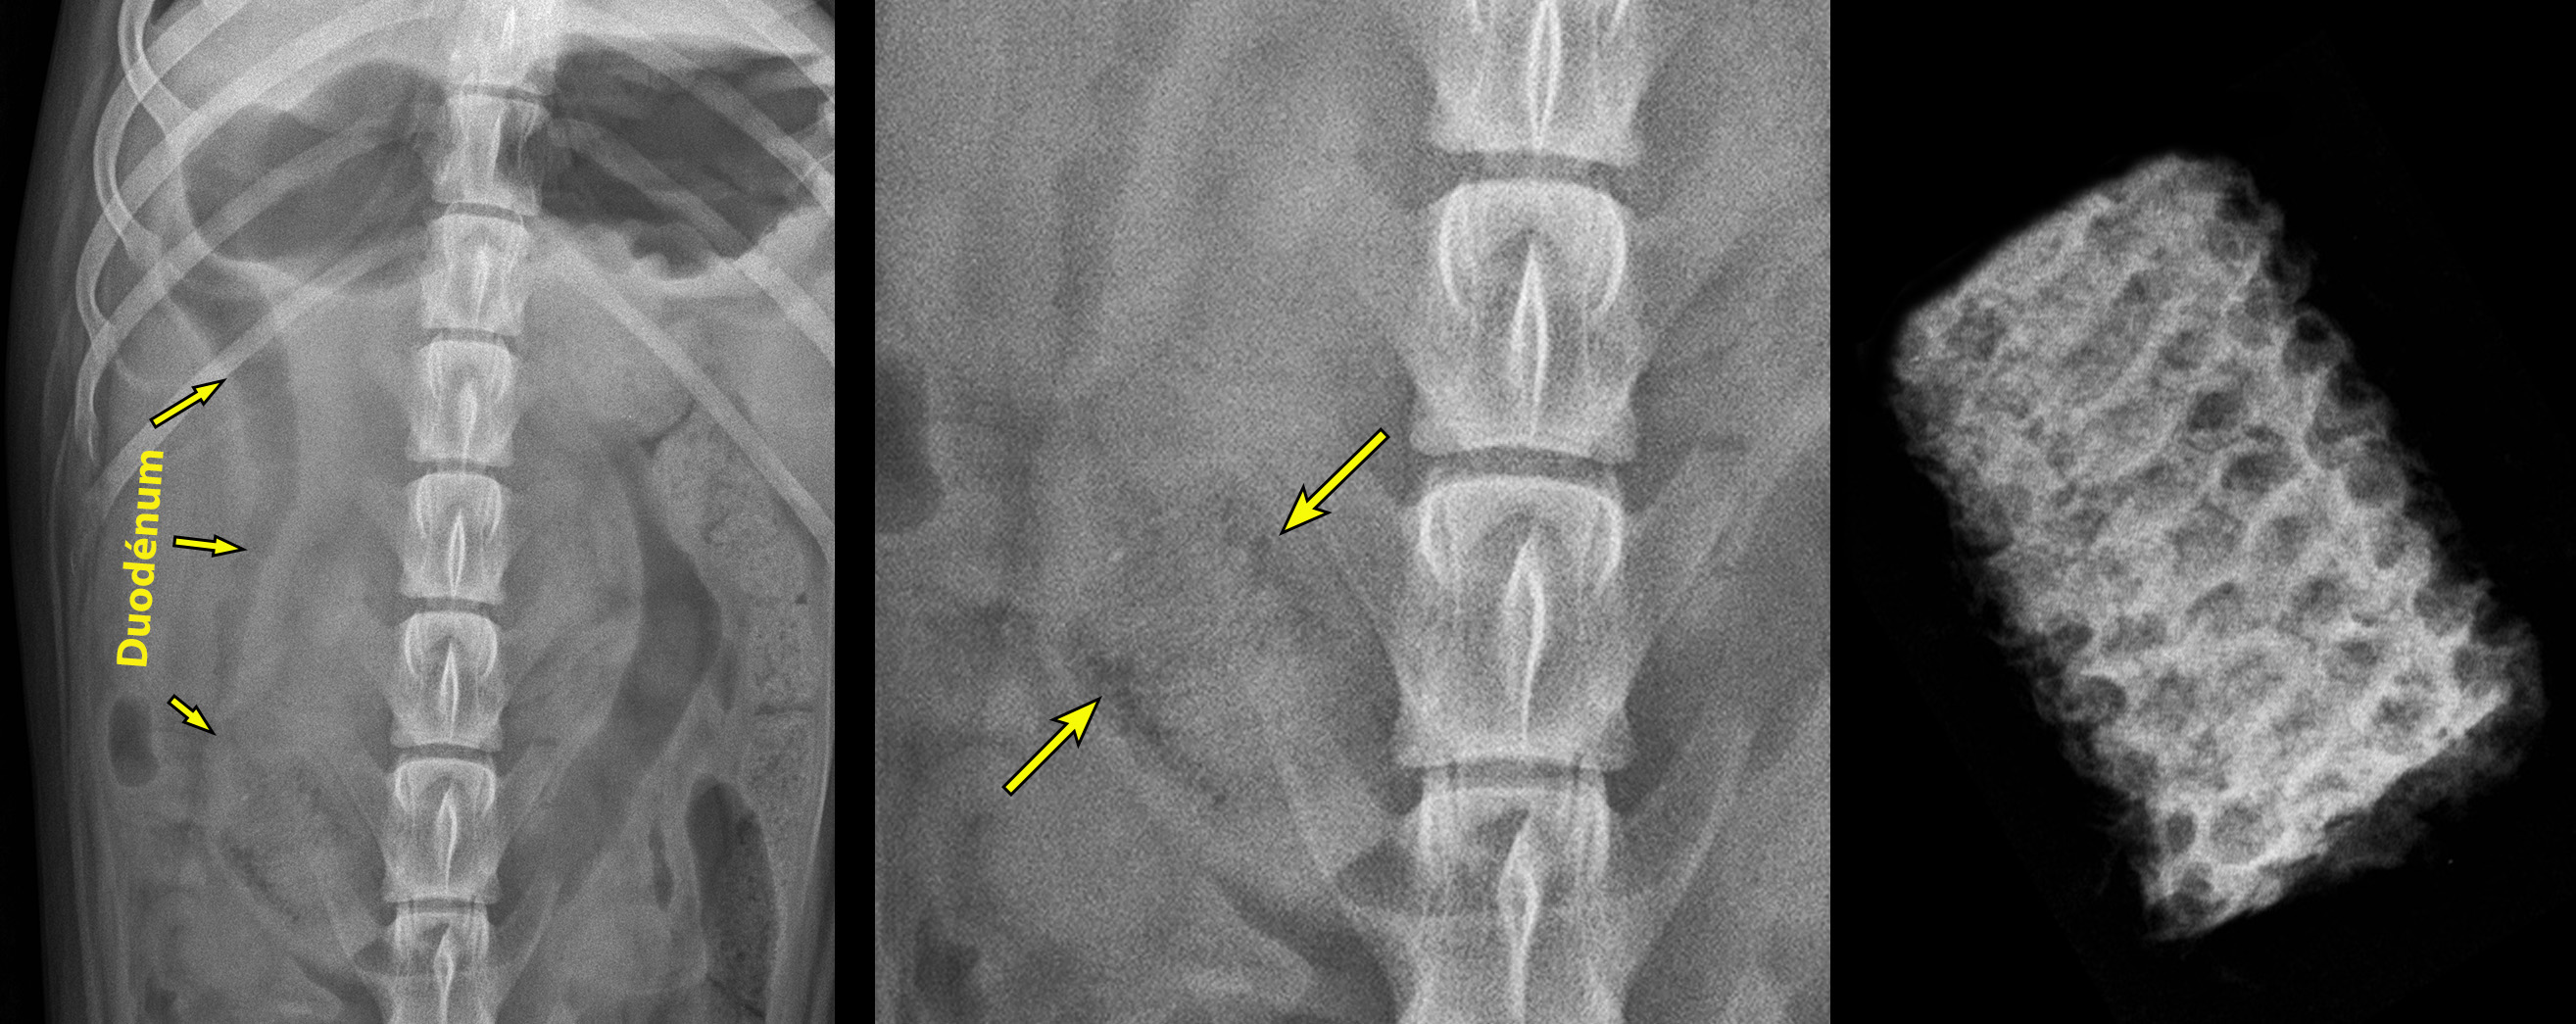

La réponse se trouvait… dans la projection VD:

Le duodénum montre une quantité excessive de liquide et d’air, formant un patron semi-fragmenté (flèches sur l’image de gauche). En portion caudale du duodénum descendant, on peut voir une structure déformant la lumière du duodénum et montrant multiples petites logettes aériques, plus évidentes en périphéries latérales (flèches sur l’image centrale magnifiée). L’apparence de cette structure est compatible avec un petit segment d’épi de maïs (ou de blé d’inde si comme moi vous habitez le Québec). À droite, on peut voir l’apparence radiographique d’un autre segment d’épi, celui-ci entouré d’air (gracieuseté de Kate Alexander).

Ceux qui avaient imaginé un chiffon n’étaient pas complètement fous, mais ils ont probablement confondu des matières fécales pour un corps étranger. Voilà, retenez bien cette image jusqu’en en août prochain, alors que le maïs du Québec sera bien croquant et sucré ! En tout cas, c’est ce qu’en pensait notre ami Georges W quand il a découvert qu’une tribu d’irréductibles indigènes vivait au nord de son America et produisait une étrange sorte de blé 😉